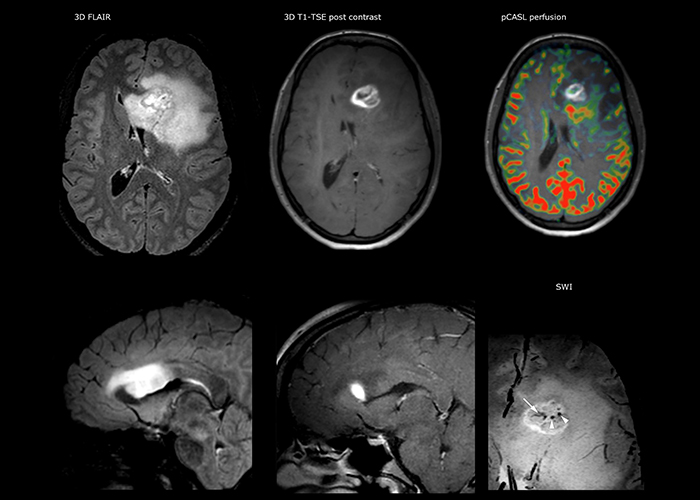

For MS imaging in the brain, Dr. Savatovsky uses 3D FLAIR as the basic sequence to visualize the lesions and assess the situation and lesion load. “We count the lesions in each location to determine if the criteria of the disease are fulfilled. We use a T2-weighted sequence because our neurologists are used to it. We compare the lesion load on FLAIR with a 3D T1 post-contrast sequence to help us determine whether lesions are old or new. We typically administer the contrast before the patient enters the machine because it shortens the examination time and allows to visualize active lesions that tend to be more visible after several minutes. When a differential diagnosis is difficult, we add sequences such as susceptibility imaging, because some focal MS lesions have a small vein in the center[3].”

“The biggest challenges are properly characterizing the lesion and giving the surgeon all the information needed, such as the location of vessels and functional areas. Sometimes a very comprehensive exam is necessary, such as when a mass has been discovered at another hospital after which the patient is referred to us. We then do both lesion characterization and preoperative imaging in one exam, so both morphologic and functional assessment. For morphologic assessment we will use pre- and post-contrast T1-weighted imaging, FLAIR to assess infiltration, and diffusion. For functional characterization we will perform perfusion, spectroscopy, and susceptibility weighted imaging to look for micro vessels or micro hemorrhage inside the lesion[4]. For preoperative imaging we perform specific morphologic imaging that is compatible with the navigation system; depending on the location of the tumor, we would do fMRI or DTI.”